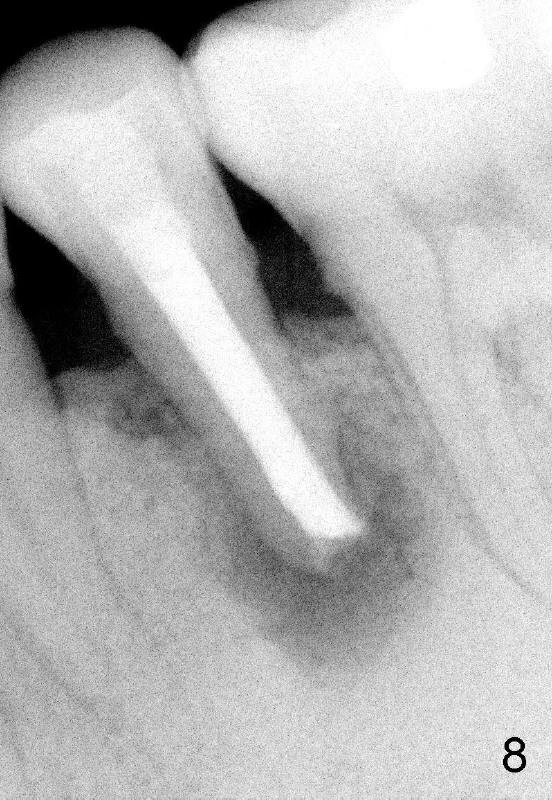

A 40-year-old Chinese man has periodic (once a month) mild pain and swelling in the lower left quadrant. Clinical exam reveals dens evaginatus (Fgi.1': <) in #20. Upon pressure from mouth mirror handle, there is limited amount of purulent discharge from the fistula (Fig.1": <). Preop PA shows a large canal with large periapical radiolucency (Fig.1). RCT started on Aug 6, 2010 with #70 file at 20 mm (Fig.2), #120 file at 16 mm (Fig.3) and CaOH paste in the canal (Fig.4). The dressing changed on Oct 8, 2010 (Fig.5). RCT finished on Jan 25, 2011 with master cone (rolled with several gutta perchae) (Fig.6), lateral condensation (Fig.7) and after vertical condensation and build-up (Fig.8). The canal was wet in the last two appointments with no sign of apexification. Follow up is done in 7 months (Fig.9), 11 months (Fig.10) and 18 months. Although the patient reports no pain after the treatment, the fistula remains with purulent discharge. The patient does not accept apical surgery. What should we do? Retreat with MTA (1,2,3)?